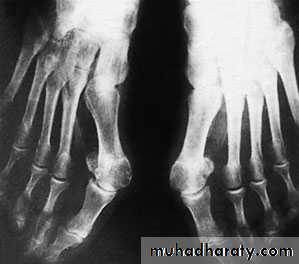

Hallux valgus:

It’s the commonest foot and musculoskletal deformity seen in practice.There is valgus deviation of the big toe with mild medial rotation where the nail facing slightly to the medial side, there is also overcrowding of the other toes with the 2nd. Toe usually develops the deformity known as hammer toe (extension of the metatarsophalangial joint, flexion of the proximal interphalangial and extension of the distal interphalangial joint).

Metatarsus primus varus: there is forefoot splaying with excessive primary varus position of the 1st. metatarsal bone that predispose for lateral deviation of the big toe during shoe wear.

X-ray:

Taken with the patient standing to show the degree of metatarsal and hallux angulations.Also it shows the state of the joint being normal, arthritic or subluxated.